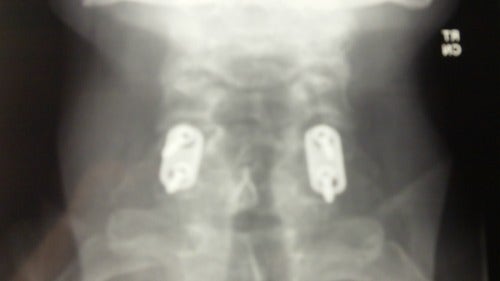

Photo: Author

I spent 18 hours in the ER and many more in surgery. They completely removed two cervical vertebrae that had shattered into more than 150 pieces. Four disks were taken out. Every other disk in my spine was ruptured. Parts of my hips were removed and shaped into spacers, which were fused with the remaining vertebrae.